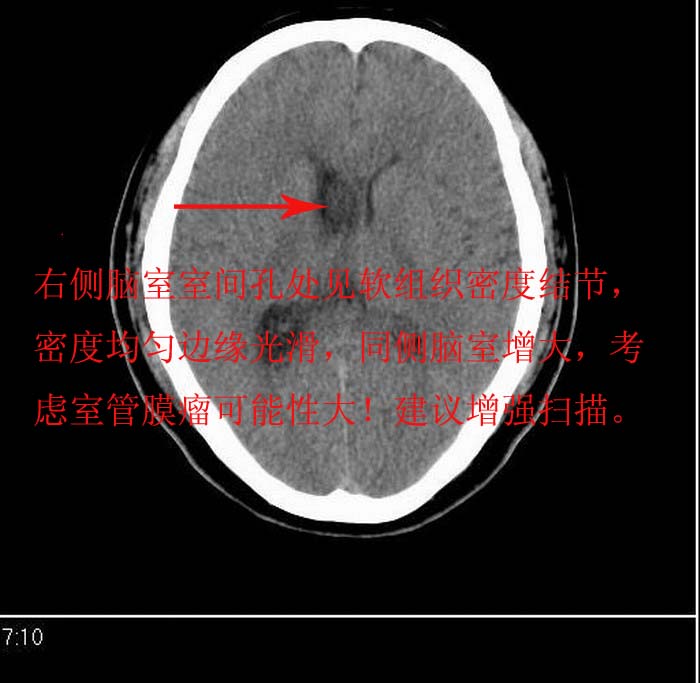

以下是引用zhengfaming在2008-5-3 20:30:00的发言:[br]右侧侧脑室室间孔处似可见等密度结节影(图2),右侧侧脑室扩大,考虑占位.以室管膜瘤可能性大

以下是引用形影不离在2008-5-3 16:55:00的发言:[br]考虑右侧侧脑室室间孔处胶样囊肿,并右侧侧脑室积水扩张。